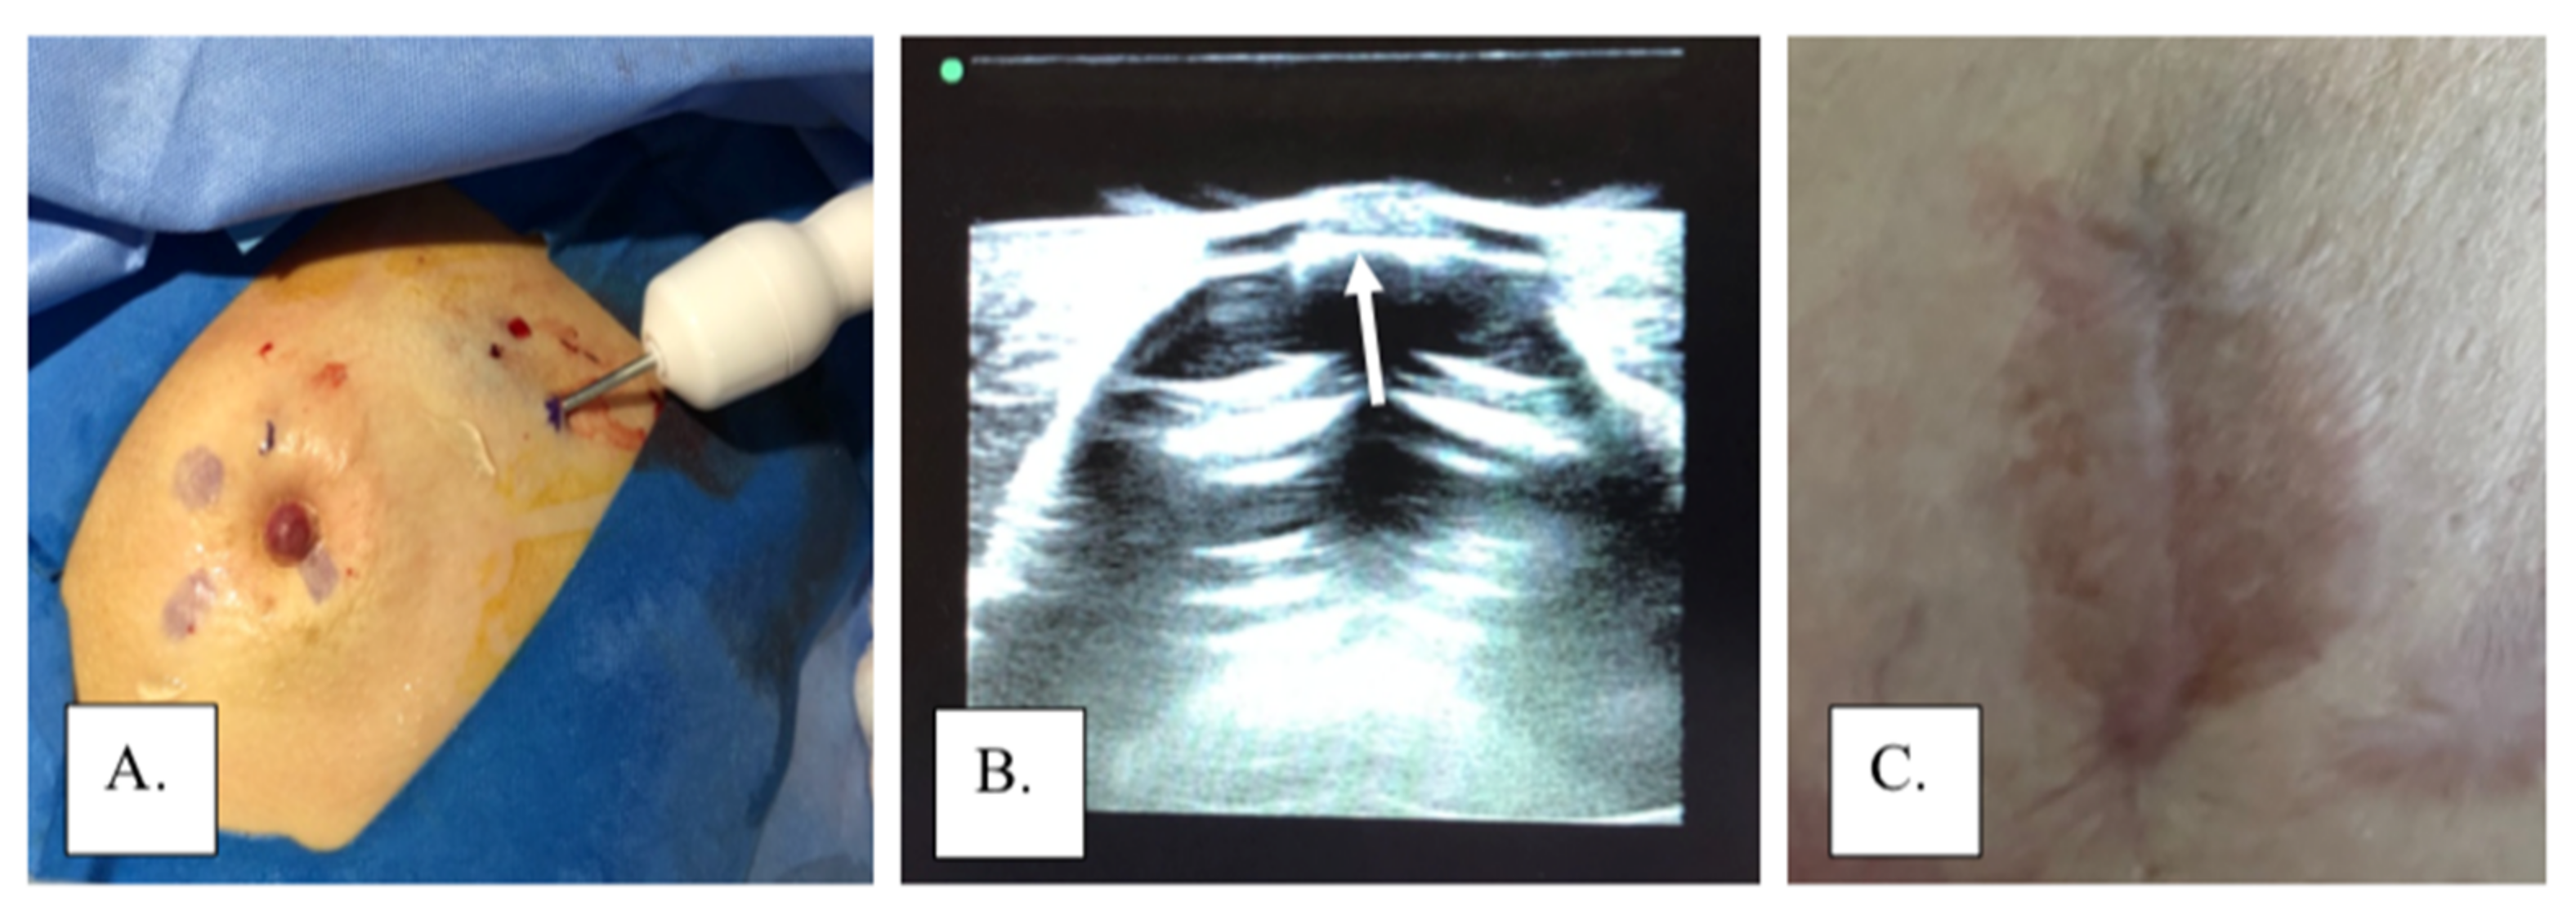

4. Work-Up

5. Treatment